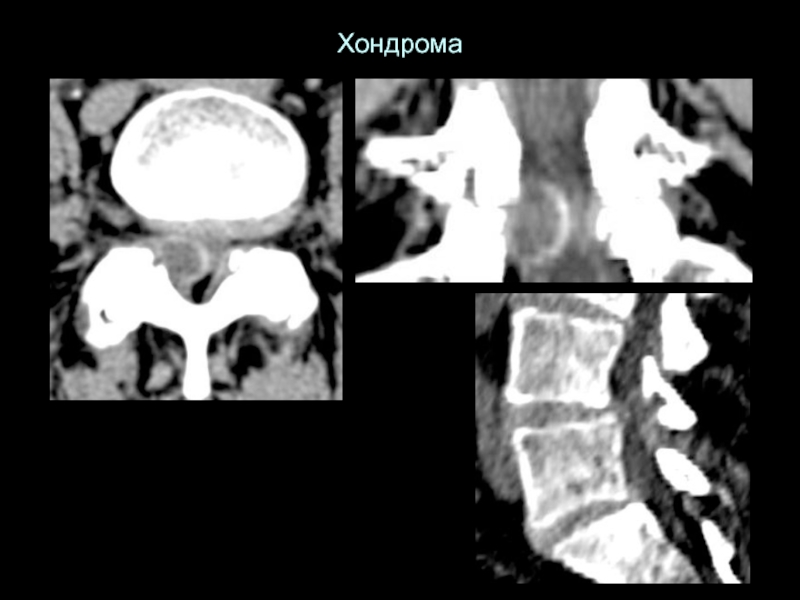

Слайд 28Хондрома

Хондрома